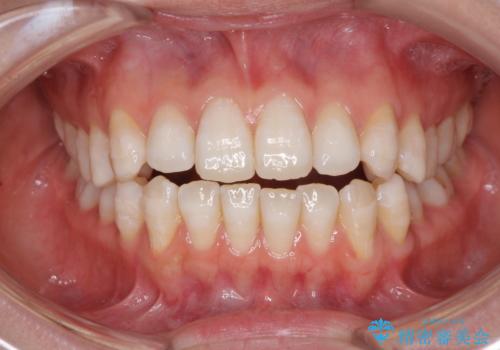

上下前歯の距離が大きかったため、上下の歯が接触するまでに時間がかかりました。

それでも目安である2年半で終えることができ、患者様には大変満足していただけました。